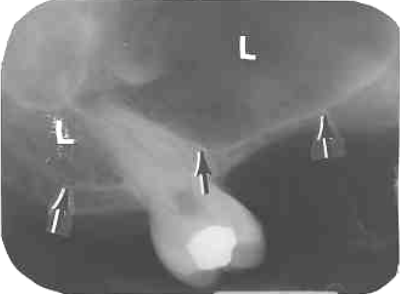

26. What is shown by L?

27. What is L showing?